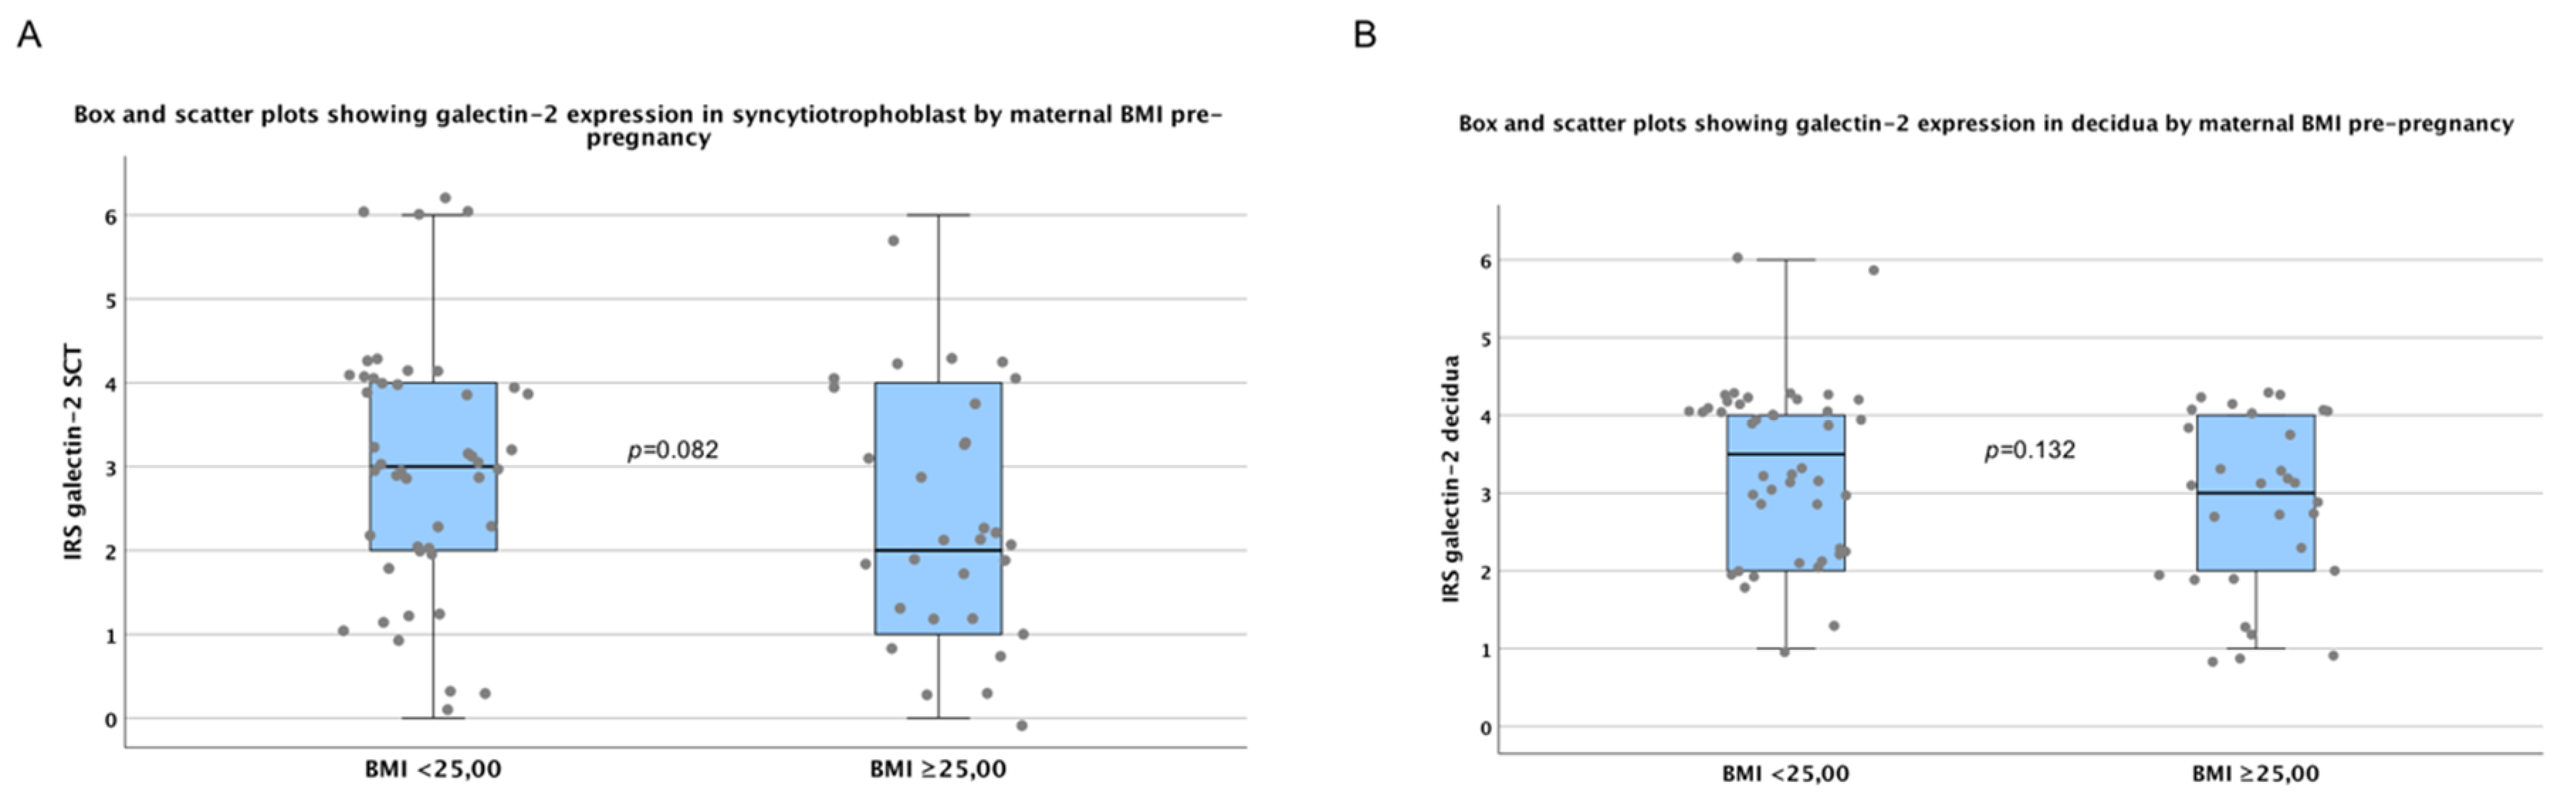

2.4. There are No Significant Differences in Galectin-2 Expression between Normal and Overweight Pregnancies